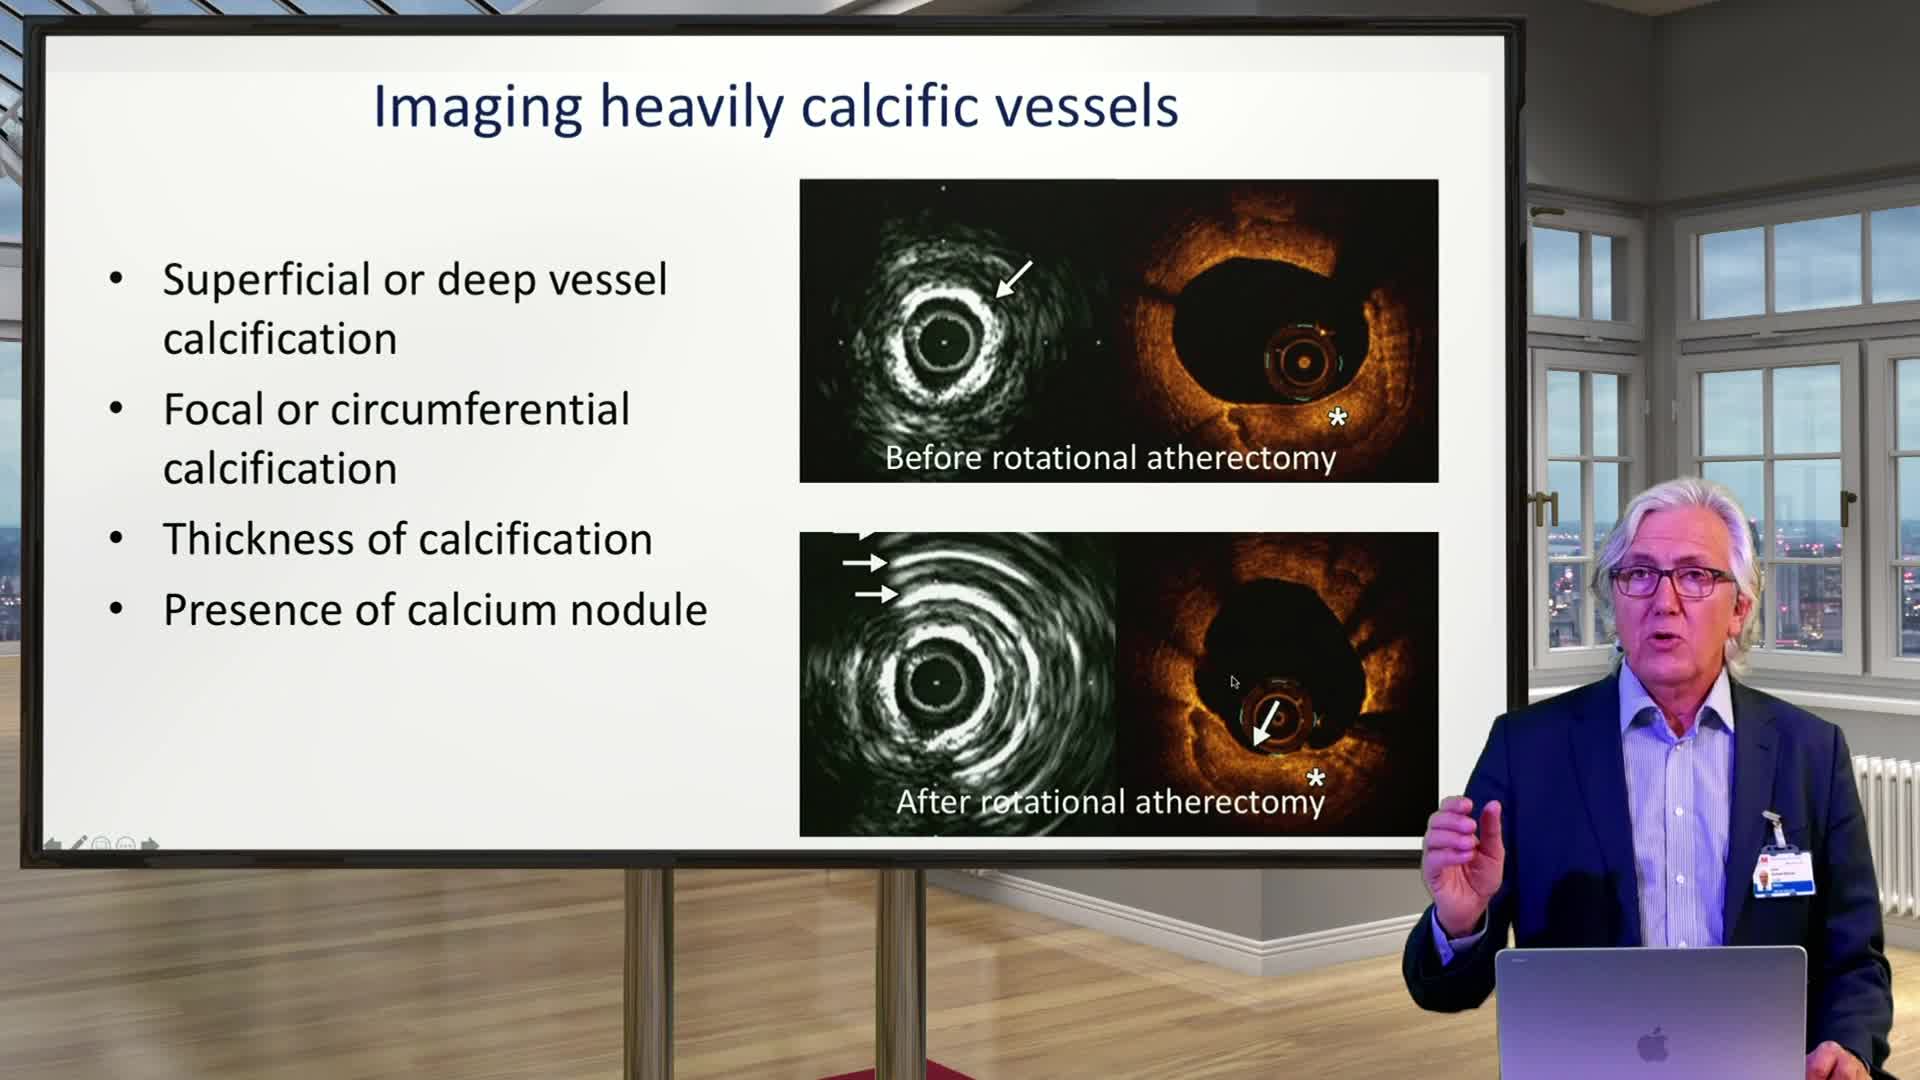

Advances in Co-registration, Coronary Physiology & Intra Coronary Imaging - April 2024 Day One

Advances in Co-registration, Coronary Physiology & Intra Coronary Imaging - April 2024 Day Two

Advances in Co-registration, Coronary Physiology & Intra Coronary Imaging - November 2023 Day One

Advances in Co-registration, Coronary Physiology & Intra Coronary Imaging - November 2023 Day Two

Advances in Co-registration, Coronary Physiology & Intra Coronary Imaging - November 2022 Day One

Advances in Co-registration, Coronary Physiology & Intra Coronary Imaging - November 2022 Day Two